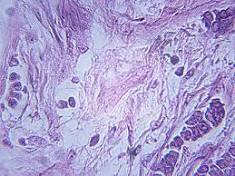

'Ecologically Diverse' Breast Cancer Carries Worse Prognosis Patients with high-grade breast cancers that have a diverse and complex microenvironment are likely to have a worse prognosis than patients with ...